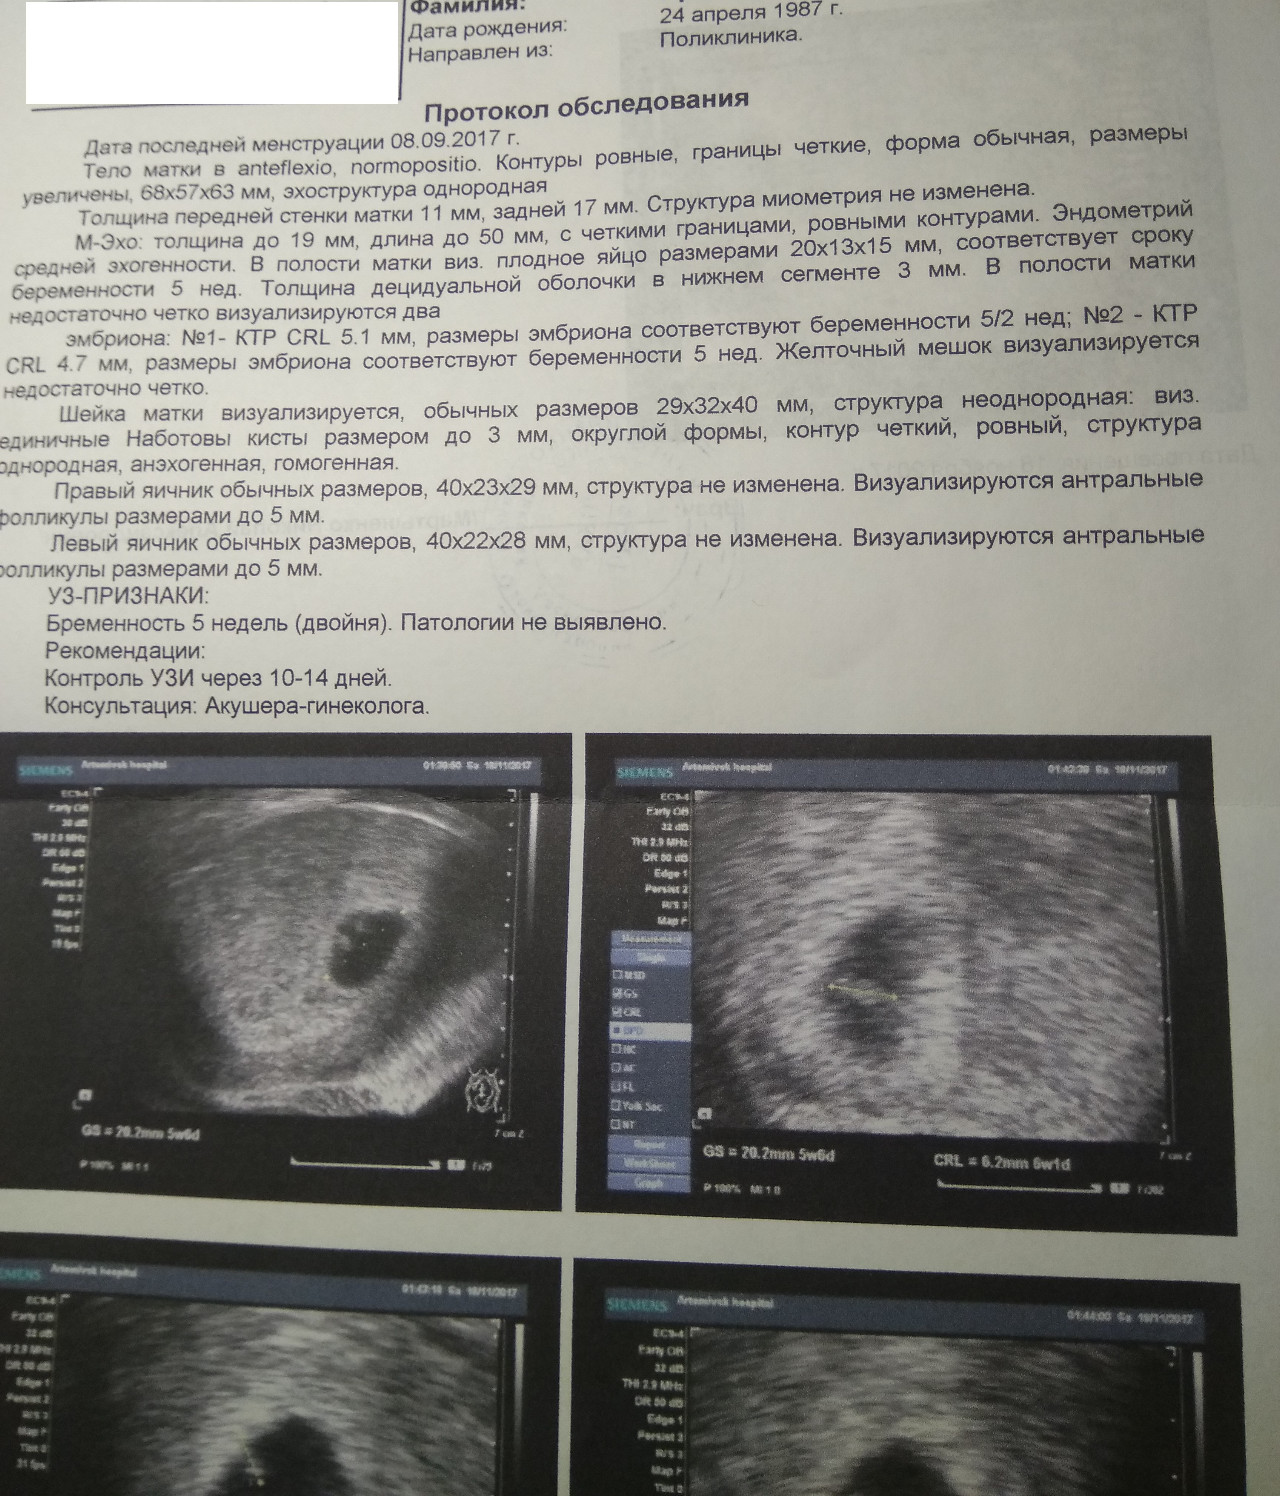

УЗИ двухплодной беременности на 5 неделе: Подборка изображений

Раздел: Калейдоскоп образов